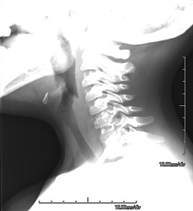

- RX Columna cervical

Técnica mediante la cual, utilizando rayos X, se obtienen imágenes de la columna cervical para su estudio. Indicaciones: traumatismo, contractura cervical, dolor articular.

Técnica mediante la cual, utilizando rayos X, se obtienen imágenes de la columna cervical para su estudio. Indicaciones: traumatismo, dolor cervical.